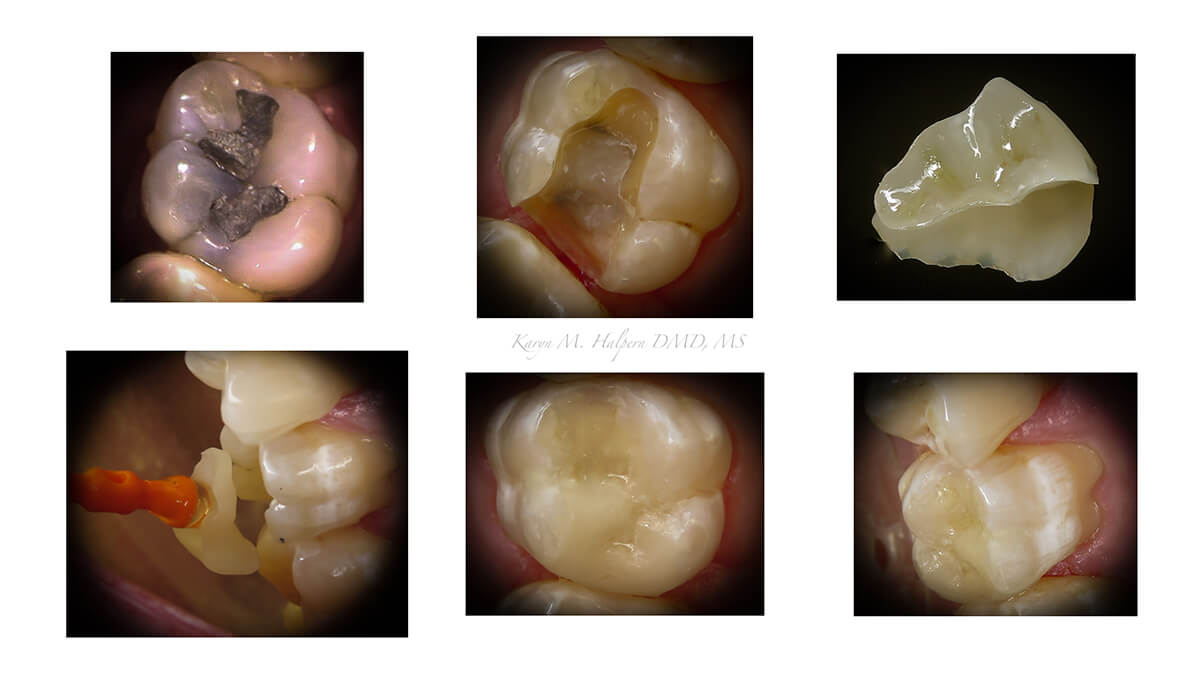

Our patient’s new crown (below) was fabricated chairside in a single session. Each crown’s design and restoration is 100% custom and designed to treat your specific dental needs while remaining both long lasting and visually pleasing.

Before

Mising composite filling with additional ridge and wall cracks.

After

A beautiful, full-surface glass-ceramic crown.